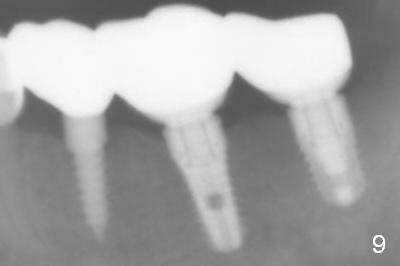

The patient is doing well postop, but 1 month postop, she complains of pain in the left submandibular area. When the immediate provisional is removed, the gingiva between the implants is erythematous (Fig.5 ^). The provisional is modified with accentuated grooves between the margins of the implants (Fig.6 *) with oral hygiene instruction. In fact the provisional is not cemented so that it is easy for self cleansing. There is crestal bone resorption 3 months postop (Fig.7,8). No further bone loss 1 year post cementation (Fig.9, cropped from pan). The bone density around the implants increases 2 years 8 months post cementation (Fig.10).